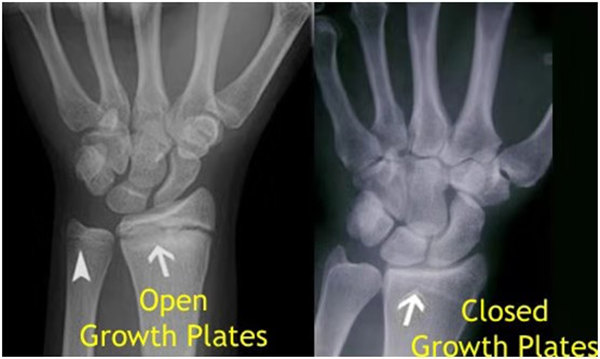

其實(shí)想要了解孩子的生長發(fā)育情況或者說孩子未來身高的趨勢,測骨齡是個(gè)好辦法。臨床上通常拍攝兒童的左手正位X光片 , 采用《中華-05》骨齡標(biāo)準(zhǔn)對(duì)手腕骨發(fā)育程度進(jìn)行骨齡評(píng)價(jià)。

我們都知道,人體的高矮是由骨骼的生長發(fā)育決定的,特別是下肢長骨。長骨呈長管狀,在長骨的兩端有一種專管骨骼生長的骺軟骨,它與干骺端之間有一盤狀軟骨結(jié)構(gòu)稱為骺板(線),在幼兒的X光片上表現(xiàn)為一條較寬的透光帶。 (見下圖)

未成年時(shí)隨著年齡的增加骺軟骨端不斷骨化,骨骼就不斷增長。當(dāng)骨骺線完全閉合時(shí)骨骼就停止生長,個(gè)子也就不再增長了。一般骨骺端完全閉合的年齡是18~20歲左右。